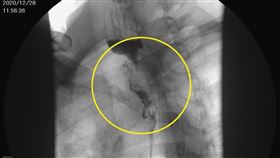

63歲男聲音沙啞喉嚨卡卡 就醫竟罹癌4期

台中一名63歲王姓男子,近來一直覺得聲音沙啞、喉嚨卡...

「喉嚨卡卡」拖半年 醫師一看:末期了

食道癌被稱為「無聲殺手」,不易早期發現,許多患者確診...